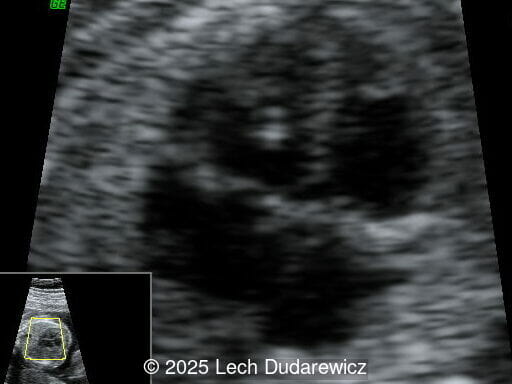

Structural anomalies were observed in multiple organ systems. The fetal skeleton showed hypoplastic iliac bones, rib deformities, hypoplastic scapulae, and excessive cervical spine lordosis. The fetal hands exhibited abnormal alignment of the fingers with restricted movement, and both feet were clubbed. Subcutaneous edema was noted over the forehead and occiput with a small cystic hygroma, along with increased nuchal fold thickness at 5.6mm, indicative of soft tissue edema. Additional abnormalities included mild pyelectasis. The fetal stomach appeared nearly empty, likely reflecting impaired swallowing or associated anomalies. Polyhydramnios was also noted. External male genitalia appeared normal. Cardiac evaluation revealed multiple echogenic foci within the left ventricle and an atrioventricular septal defect. While the heart's overall structure and function were otherwise normal, these findings added to the overall suspicion of a syndromic condition.

Other findings on prenatal ultrasound include soft tissue edema, facial anomalies, cardiac defects, and renal abnormalities. Soft tissue findings, including increased nuchal fold thickness and generalized subcutaneous edema, are common in campomelic dysplasia. Macroglossia and facial dysmorphisms, such as a flat nasal bridge or hypertelorism, may be observed but can be subtle on prenatal imaging. Polyhydramnios, frequently noted in affected pregnancies, may result from impaired fetal swallowing due to craniofacial or neurologic abnormalities. Cardiac anomalies, while not pathognomonic, include ventricular septal defects and echogenic intracardiac foci. Renal abnormalities, such as pyelectasis or enlarged kidneys, may also be present. These findings, although non-specific, contribute to the syndromic picture of campomelic dysplasia.